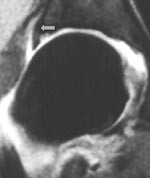

Tabell 1 viser våre funn. Labrum ble tydelig fremstilt på alle MR-artrogrammene. Normal labrum er triangulær i tverrsnitt og med lavt signal. Den er tynnere anteroinferiort og tykkere posterosuperiort. Nedad går den sammen med ligamentum transversum. Den perilabrale recess sees normalt superiort hvor leddkapselen hefter seg noen millimeter over øvre del av labrum (fig 2). Denne recess er mye mindre anteriort og posteriort.

Degenerativ labrum viste økt signalintensitet i labrum uten affeksjon av overflaten med inntakt recess hos to pasienter (fig 3) og med manglende fremstilling av recess hos tre pasienter (fig 4). Sistnevnte ansees forårsaket av labrumhypertrofi. Labrumruptur ble diagnosisert hos ti pasienter. Ruptur ble beskrevet når man kunne identifisere kontrast mellom labrum og acetabulum (fig 5) eller imbibering av kontrast i labrum (fig 6). Alle rupturene satt i øvre del av labrum.To av disse pasientene er operert, og vårt funn ble verifisert. Begge var aktive fotballspillere, og de hadde henholdvis stadium 2B og stadium 3B ved MR-artrografi. Dette samsvarte med de artroskopiske funn. Den tredje pasienten som er operert, viste forandringer forenlig med villonodulær synovitt. Også dette ble verifisert ved artroskopi (fig 7).